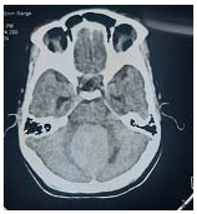

#Case 7:

This 40 years male, off work, experience history of long duration headache and impaired hearing over the last few years, few months before his coming, he developed difficult in swallowing, nasal regurgitations and diminish hearing in his Rt ear.

On clinical evaluation; patient looks unwell, severe loss of weight, slurred speech spastic Rt side hemiplegia that the power grade 3.

Operation: Ventricuol-perotenial (VP) shunt anterior approach was done, patient showed good recovery from anesthesia but few hour post operative he developed drop in the level of consciousness that GCS was 7/15and agitated. After speaking to the family clearly about the new situation and explain the complications of the coming surgery, the decision of crainectomy was made. Patient was taken urgently to the operating room, and on lateral side position, and through far lateral craniectomy, intra operative; cyst containing oily like fluid and soft part. Macroscopic total excision was made.

Post operative, the patient recovered well from anesthesia, taken to the ICU on nasal oxygen mask. In the first post operative day, he regains his conscious, communicate with the surrounding.

Histopathology

Pilocystic astrocytoma.

Patient discharge in good condition, NG for feeding to prevail over the nasal regurgitations and improve gastric feeding, but still having Rt side weakness.